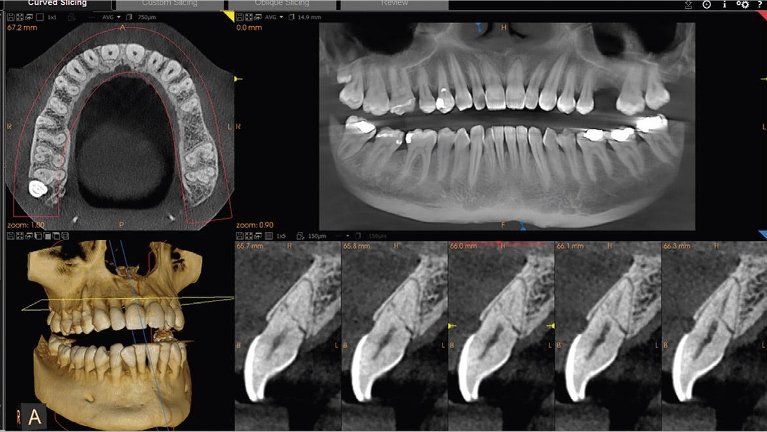

La TAC Cone Beam in dotazione al Centro Diagnostico Avanzata rappresenta il più recente sistema di TAC dentale (TAC aperta), uno strumento che ha rivoluzionato il mondo della radiologia dentale e dell’ortodonzia. Questa nuova tecnologia permette infatti di ottimizzare il livello di esposizione ai raggi X con una notevolissima riduzione della dose (che va dalle 25 alle 90 volte) rispetto a una tradizionale TAC delle arcate dentarie (Dentalscan). Nei bambini, inoltre, la dose di esposizione può essere ulteriormente ridotta utilizzando opportuni programmi pediatrici di studio. Algoritmi di ricostruzione 3D avanzati e uniformità delle misurazioni in scala 1:1 sono in grado di fornire una panoramica dentale completa e di favorire una valutazione dettagliata dell’anatomia delle ossa mascellari e del canale mandibolare, fondamentali nel campo dell'implantologia e nella programmazione di interventi estrattivi.

Oltre agli strumenti citati per effettuare la panoramica dentale completa, il Centro Diagnostico Avanzata di Cortona, provincia di Arezzo, dispone di un tomografo FONA. Tale strumento è in grado di fornire una valutazione dettagliata dell’anatomia, delle strutture ossee del massiccio facciale